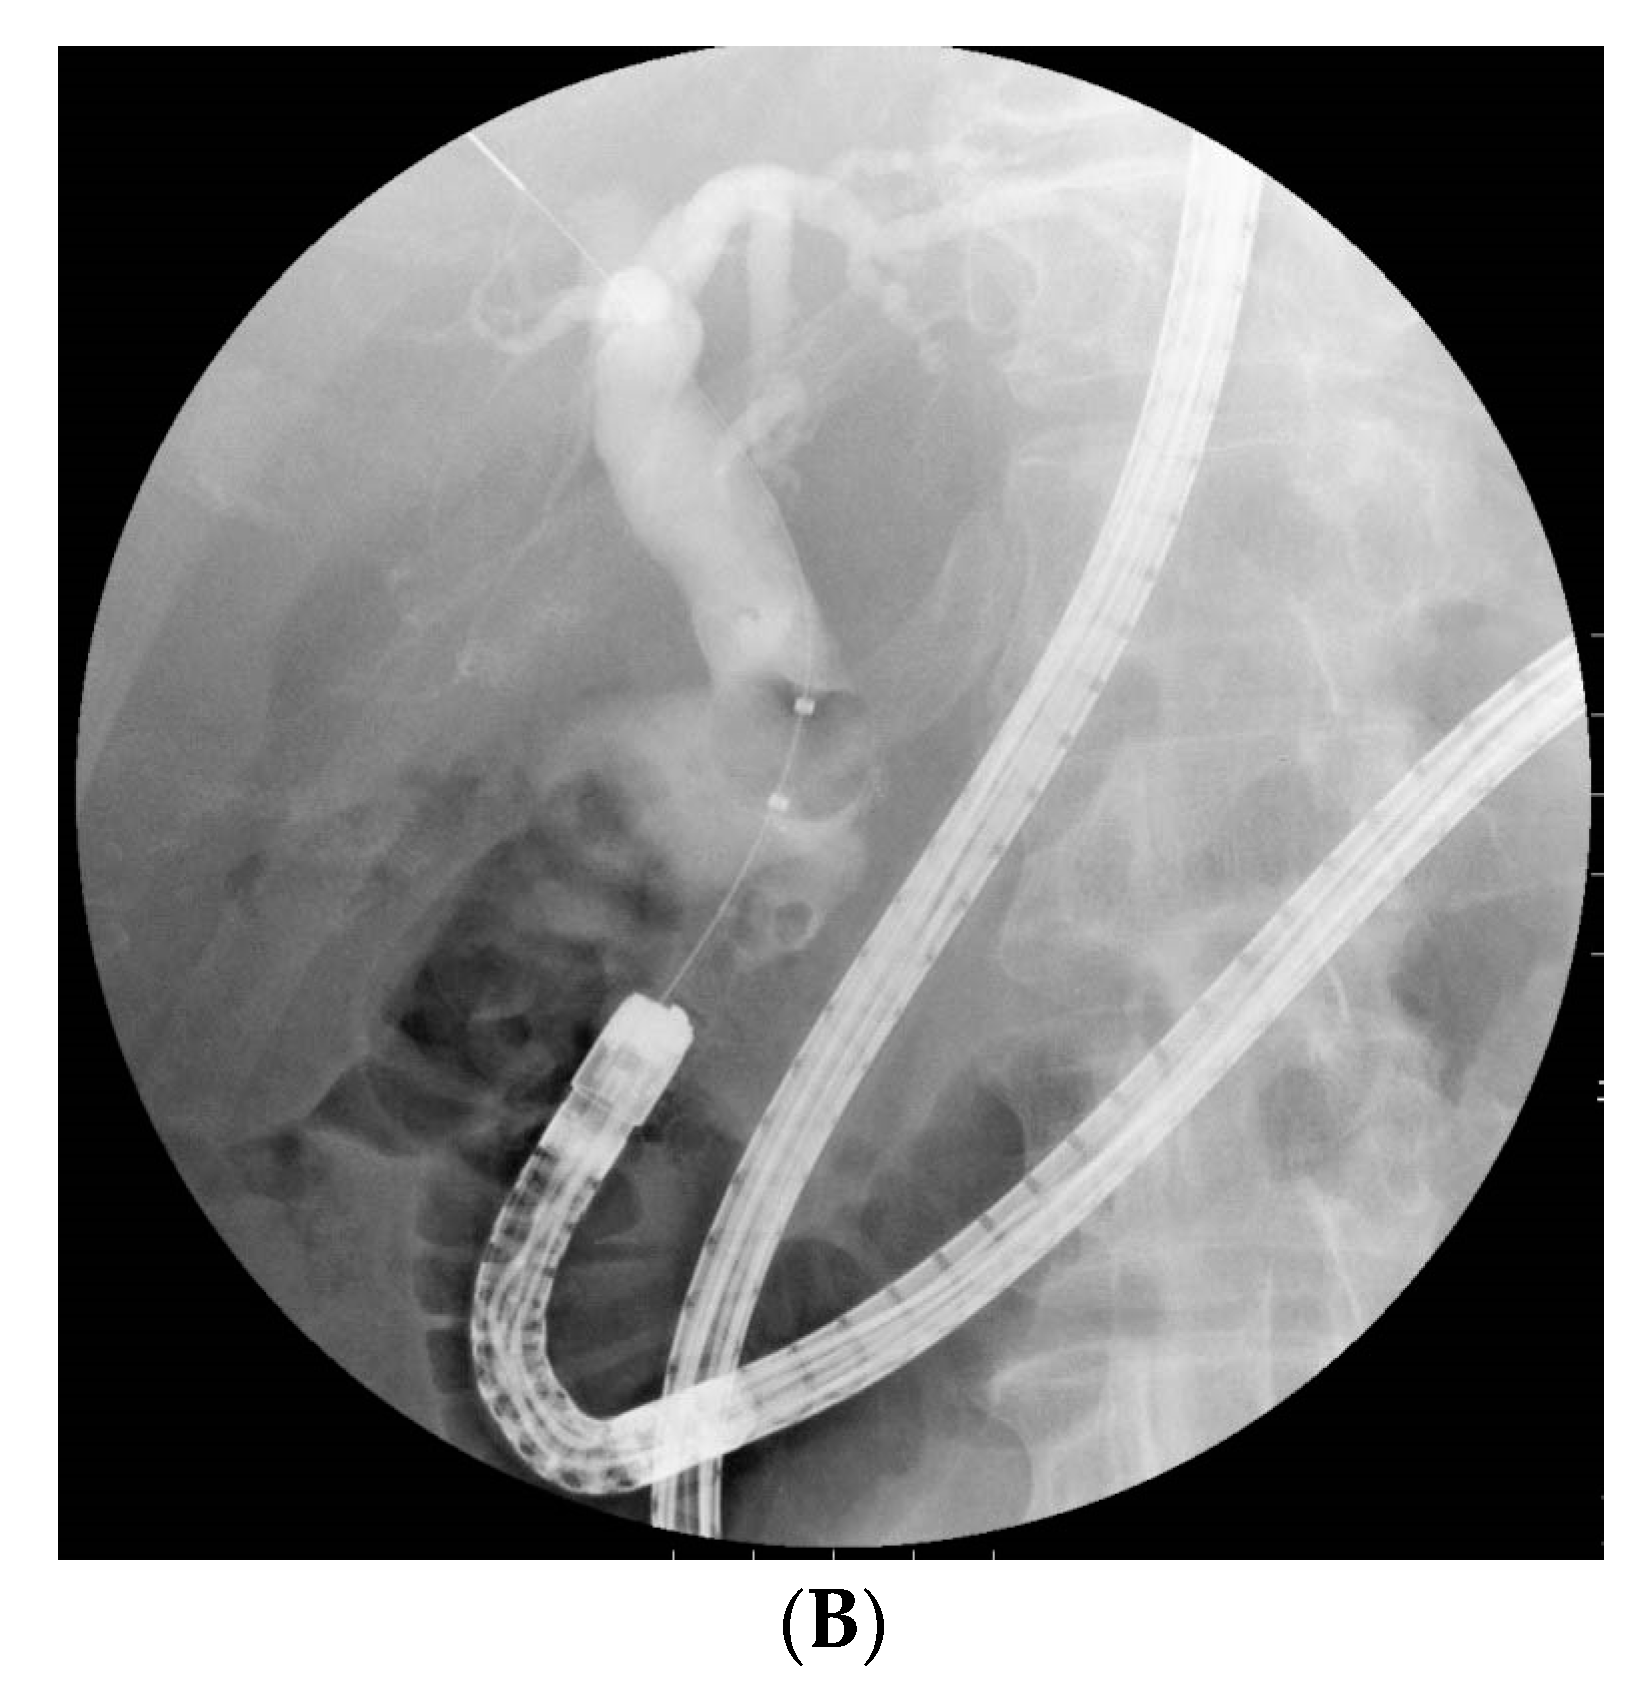

2.3. BE-ERCP Procedure

3.3. Ampullary Procedure for Stone Extraction at Initial BE-ERCP

3.4. Biliary Intervention and Complete CBD Stone Extraction in an Initial BE-ERCP